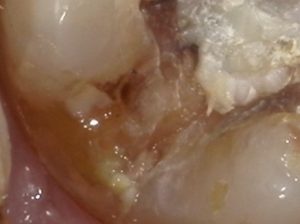

しかし臨床の現場で診断に悩む多くの破折はクラックの段階のケースである。次の写真は腫れてきたが他院で原因不明と言われたケースだがインレーを除去すると中はひどいカリエス

遠心部を拡大してもよくわからない。

カリエスを除去すると